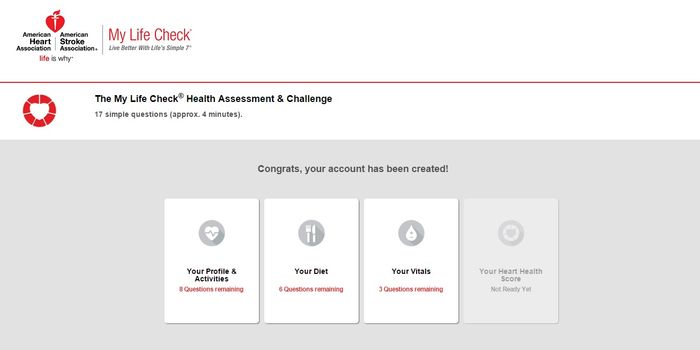

DEC 23, 2015CardiologyRecent data from the American Heart Association (AHA) confirmed cardiovascular disease as the leading cause of death in ...